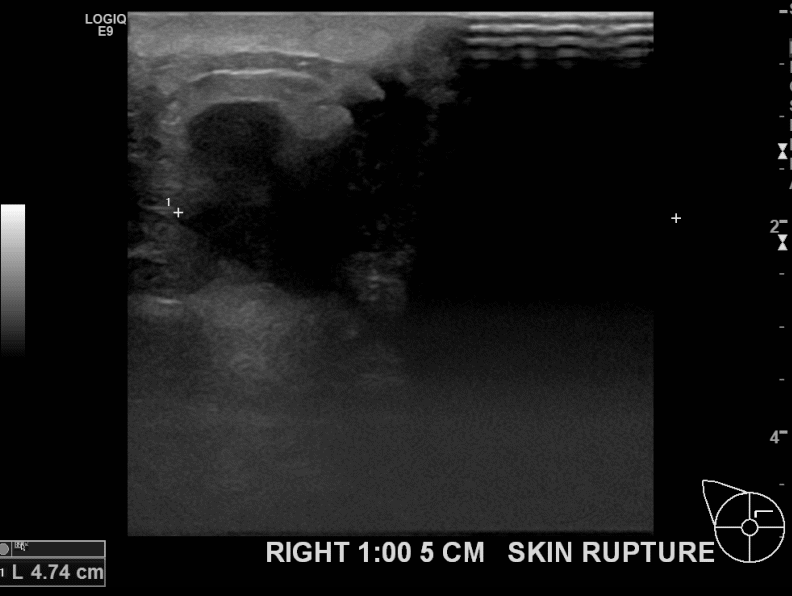

상기환자 우측에 만져지는 멍울있어 내원하신 40대 여성분으로 의심스러운 혹 조직검사 시행후 유방암진단되었습니다.